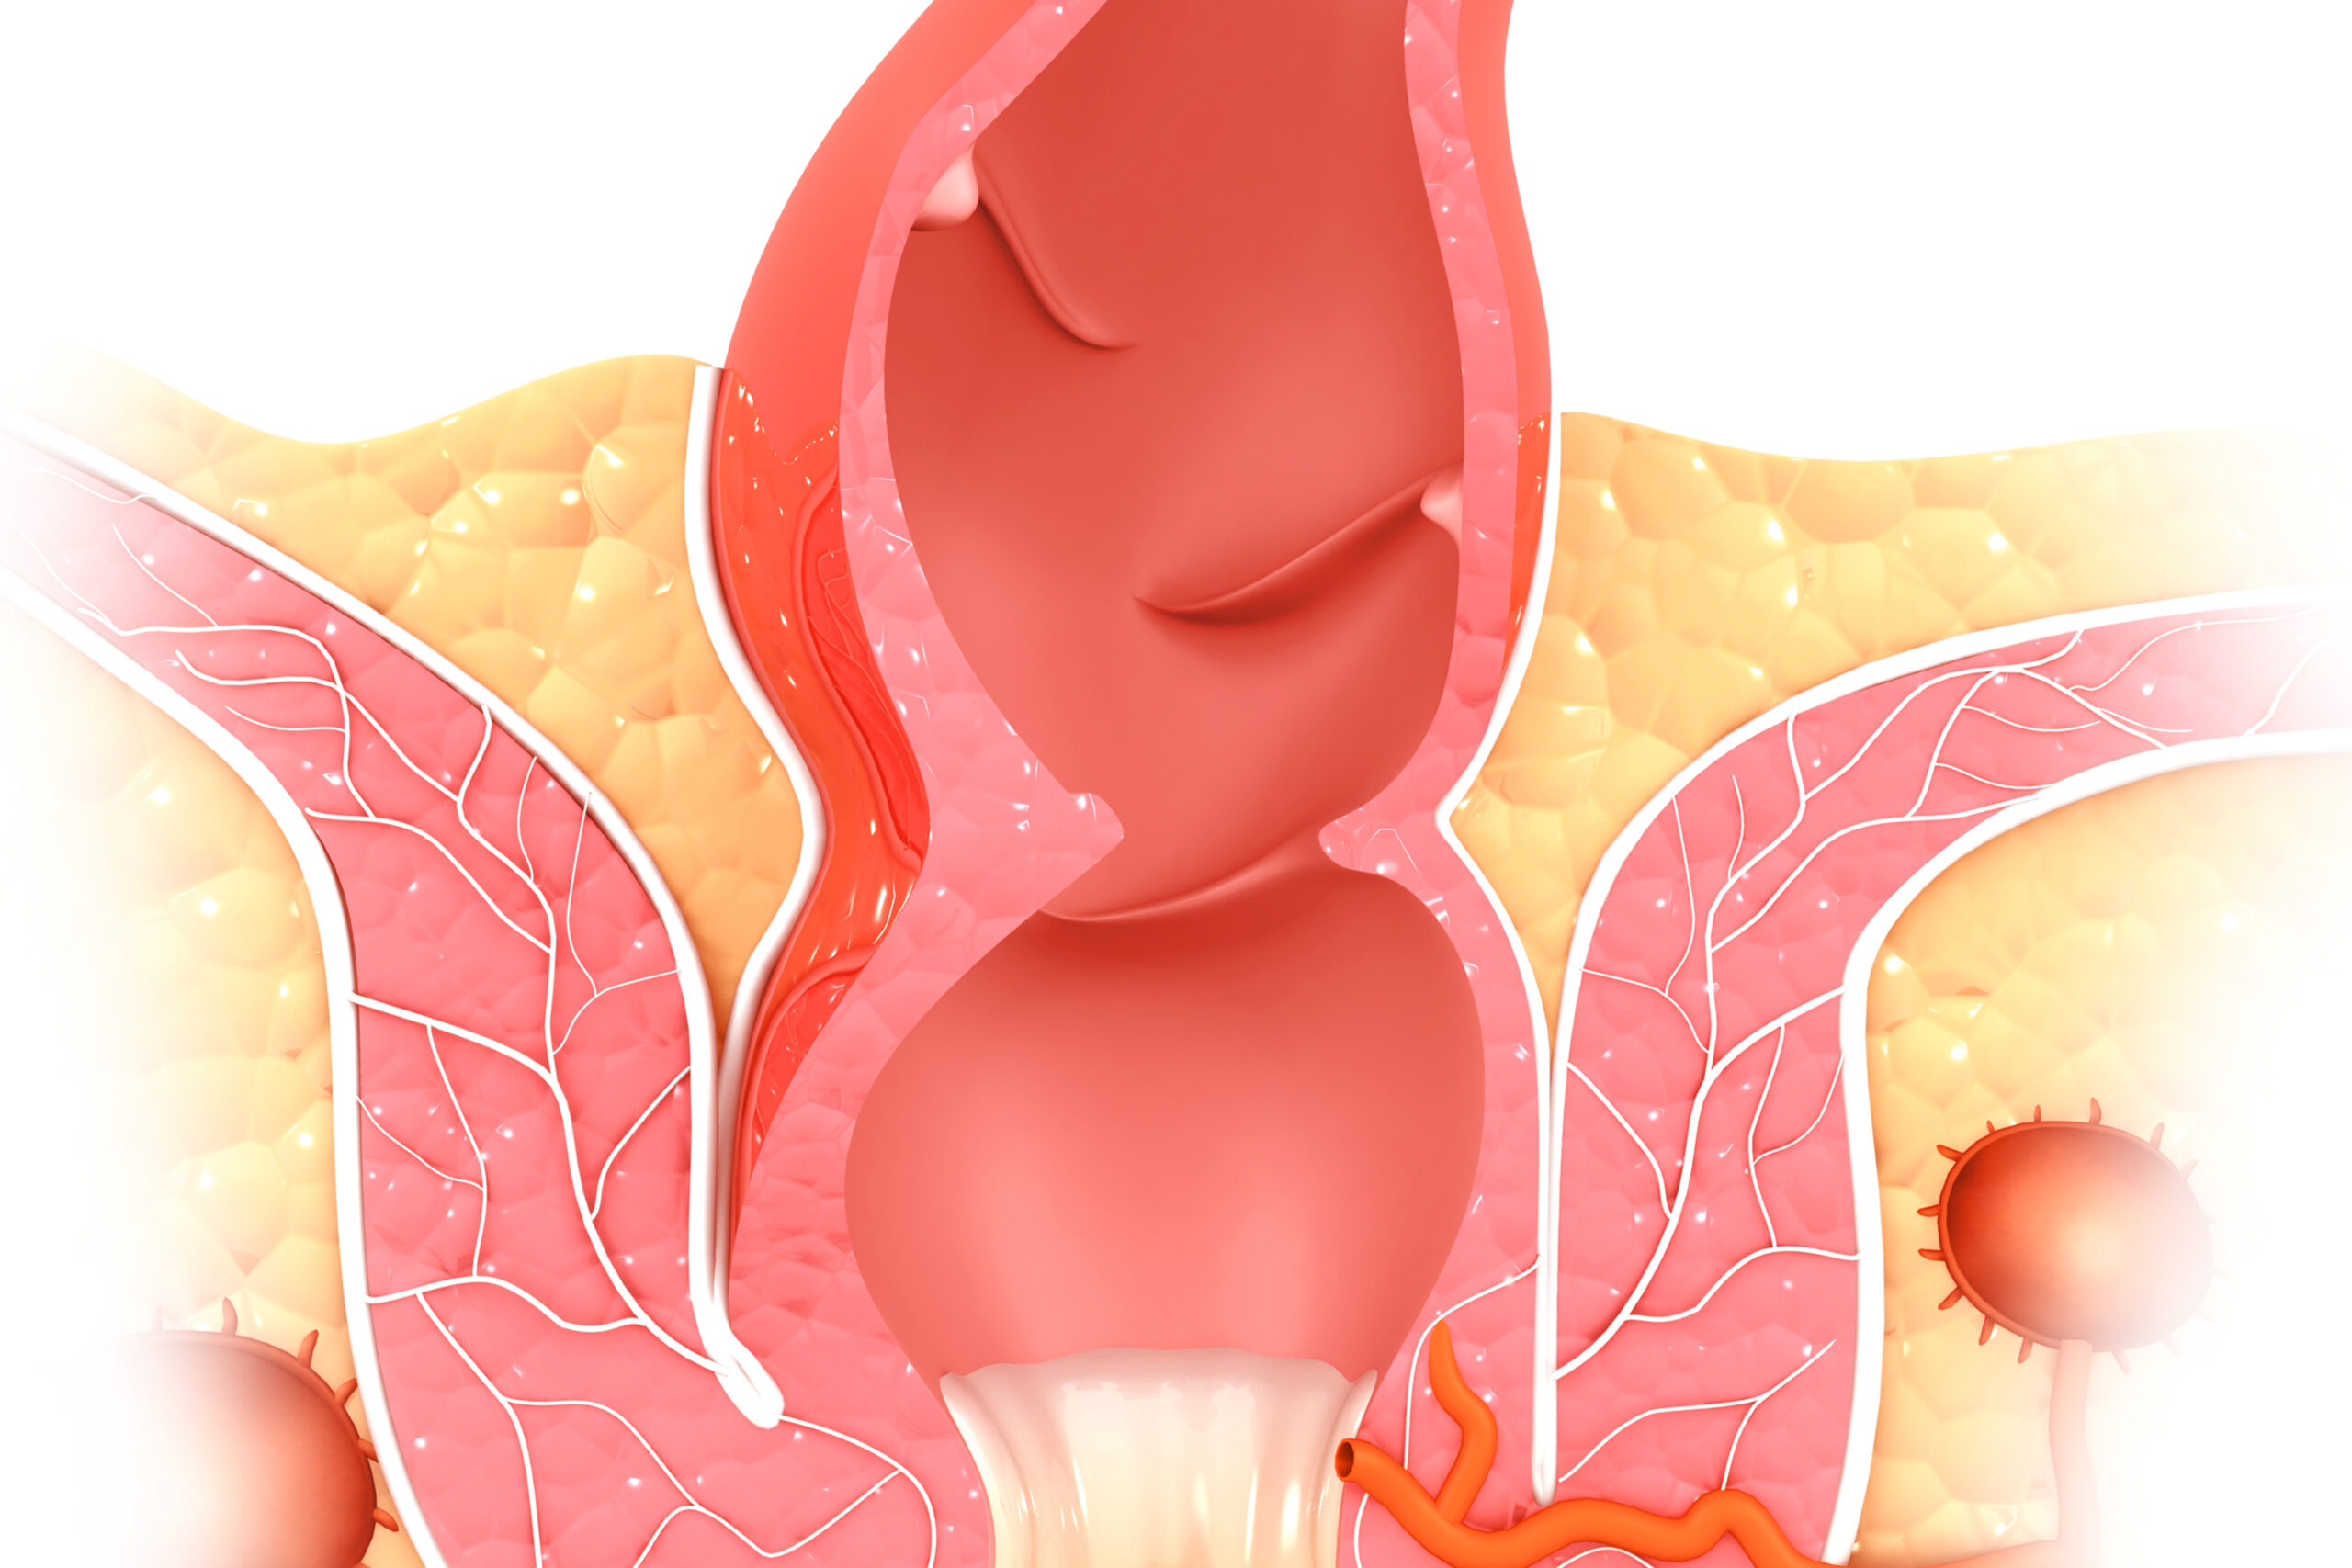

Οι γιατροί χωρίζουν τις αιμορροΐδες σε δύο διαφορετικούς τύπους – εσωτερικές και εξωτερικές αιμορροΐδες.

Οι εσωτερικές αιμορροΐδες μπορεί να απαιτούν θεραπεία, συμπεριλαμβανομένων φαρμάκων ή μη χειρουργικών μεθόδων, όπως απολίνωση με καουτσούκ. Ωστόσο, οι εξωτερικές αιμορροΐδες δεν χρειάζονται θεραπεία εκτός εάν προκαλούν δυσφορία.

Εσωτερικές αιμορροΐδες σχηματίζονται μέσα στο ορθό. Τα συμπτώματα περιλαμβάνουν:

- Πρόπτωση αιμορροΐδας: Αυτό συμβαίνει όταν μια εσωτερική αιμορροΐδα πέφτει μέσω του πρωκτού λόγω τάνυσης.

- Εάν ένα άτομο έχει πρόπτωση αιμορροΐδας, μπορεί να αντιμετωπίσει πόνο και δυσφορία. Διαφορετικά, οι εσωτερικές αιμορροΐδες δεν είναι συνήθως επώδυνες.